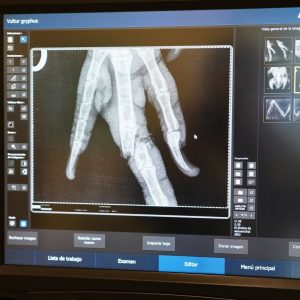

Hace unos días en Las Chacras, San Luis, se dio aviso de una cóndor hembra herida. Rápidamente, fue trasladada a Fundación Temaikèn y, después de un chequeo veterinario, se encontraron varias lesiones. Entre ellas, una fractura en un dedo que no podía recuperarse.

El equipo de veterinarios realizó la cirugía del animal en el hospital del bioparque. Ahora se encuentra bajo monitoreo a la espera de su recuperación